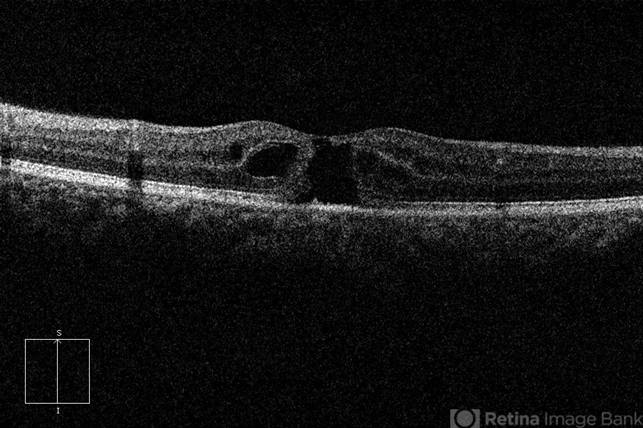

- Tamoxifen Retinopathy

- OCT image of an 58-year-old woman with a bilateral tamoxifen maculopathy. She had taken tamoxifen for 24 months due to breast cancer. In spite of discontinuation 2 years ago, her macula remained unchanged. Her best-corrected visual acuity was 20/50 in the right and 20/100 in the left.